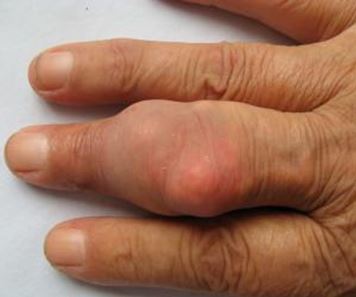

第三阶段为痛风中期,由刚开始发病时的一个脚趾关节,痛风性关节炎反复急性发作,几次急性发作以后,逐渐波及到指、趾、腕、踝、膝关节等全身关节,进而周围的软组织和骨质也遭到不同程度的破坏和功能障碍,尿酸结晶不断沉积,慢慢地形成了结石一样的“痛风石”,此时,肾功能正常或表现为轻度下降;

第四阶段为痛风晚期,患者关节畸形及功能障碍日益严重,痛风石增多,体积增大,易破溃流出白色尿酸盐结晶,由于关节永久性畸形,影响了日常学习、工作和生活,给病人带来极大地身心痛苦。尿酸盐不断沉积到肾脏里,形成肾结石等,临床出现浮肿、少尿、蛋白尿、夜尿增多、高血压、贫血等提示肾功能受到损害,肾功能明显减退。病情进一步发展,则出现不易逆转的肾功能衰竭而危及生命。